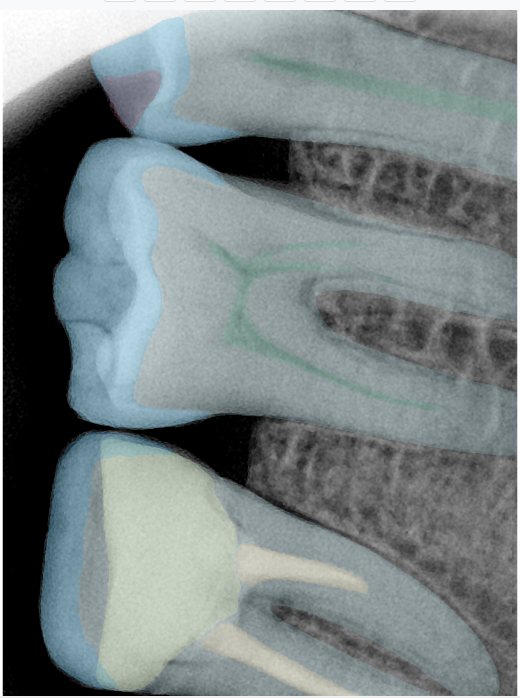

CR/DR 牙齿分割阶段记录

当前进展

- 完成了 CR/DR 牙齿相关分割训练

- 当前结果已经达到阶段预期,但仍有细节问题需要继续处理

相关测试

遇到的问题

- 训练过程中出现过 mask 下移问题

- 部分结果会出现 box 填充异常

- mask 边缘仍然有比较明显的锯齿感

参考

第二版算法问题测试